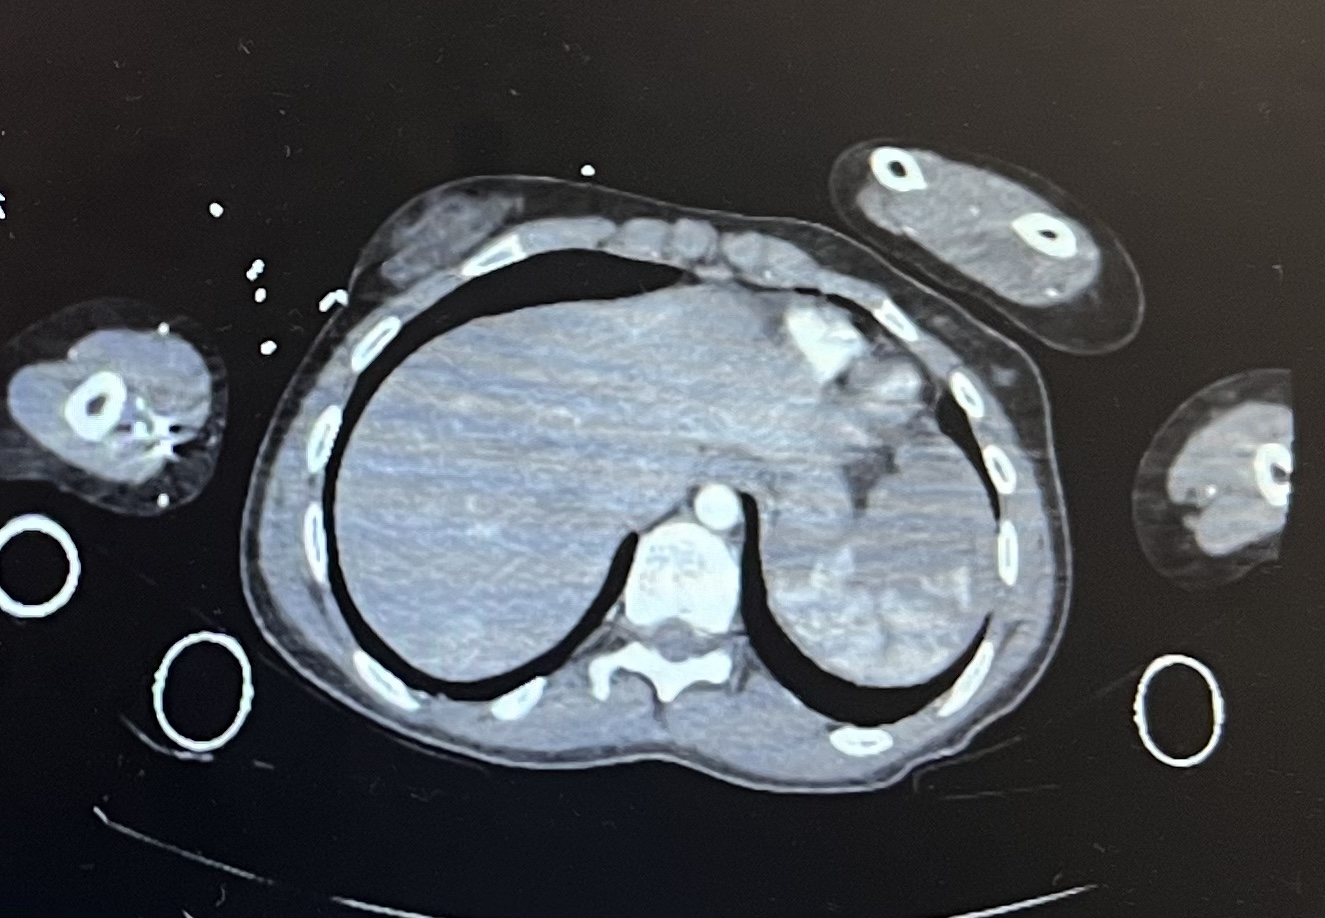

La paciente se traslada a hospital adecuado rápidamente. Se realizó Body TAC detectándose rotura esplénica grado IV. Anemización secundaria.

Durante el transcurso de pruebas la paciente debutó con hipotensión debido al mayor sangrado, pasando a Shock descompensado. Se realizó cirugía de esplenectomía urgente ante la gravedad.